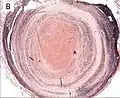

| A recent pulmonary thrombo-embolus with prominent lines of Zahn. The pale areas consist of fibrin and platelets. The red areas consist of erythrocytes. | |

Thrombus showing circumferential lines of Zahn. -